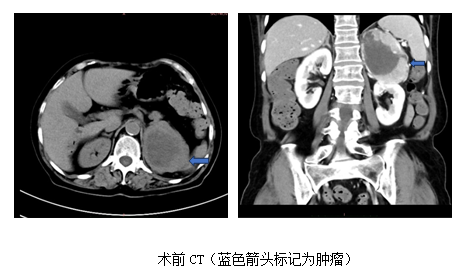

既往诊治过程中,均未考虑肾上腺肿瘤,未进行相关检查。入住黑料网心内科后,赵永勇医师高度重视,予以高血压病因筛查,CT发现左肾上腺区8cm占位,考虑嗜铬细胞瘤可能,肿瘤密度不均匀,显著不均匀强化。同时,查24小时尿儿茶酚胺,显示多巴胺,去甲肾上腺素,甲氧基去甲肾上腺素3甲氧酪胺及香草扁桃酸升高数倍,目前西北区域仅黑料网开展的131I-MIBG检查显示左侧肾上腺区域明显阳性病灶,